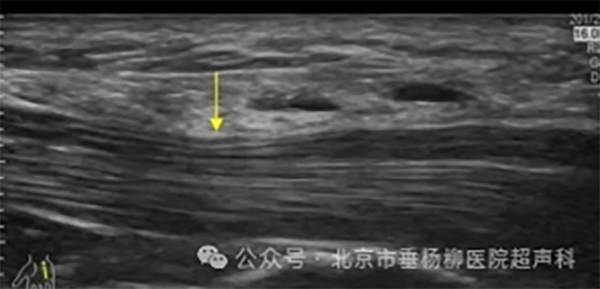

超声引导下肌骨治疗利用超声波成像技术,实时监控和引导治疗器械(如针头)定位到病变部位,进行精准的治疗性操作。超声波能够提供清晰的实时影像,帮助医生精确找到病变组织或部位,确保治疗的准确性和安全性。

超声引导:在超声影像的实时监控下,医生将治疗器械(如注射针头)精确地插入病变部位。超声波提供的实时动态影像,使医生能够清晰地观察到治疗器械的位置和周围的组织结构。

精准治疗:医生在超声引导下,将药物或其他治疗物质直接注射到目标区域,实现精准治疗。常用的注射物包括局部麻醉剂、类固醇、透明质酸、血小板富血浆(PRP)等。